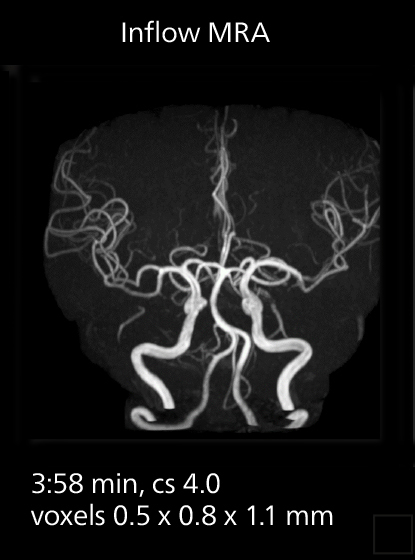

MRI of prostate

Examples of prostate imaging showing faster scan times and improved resolution illustrate the power of SmartPath to Elition X in this case of prostate cancer with PI-RADS score 4.